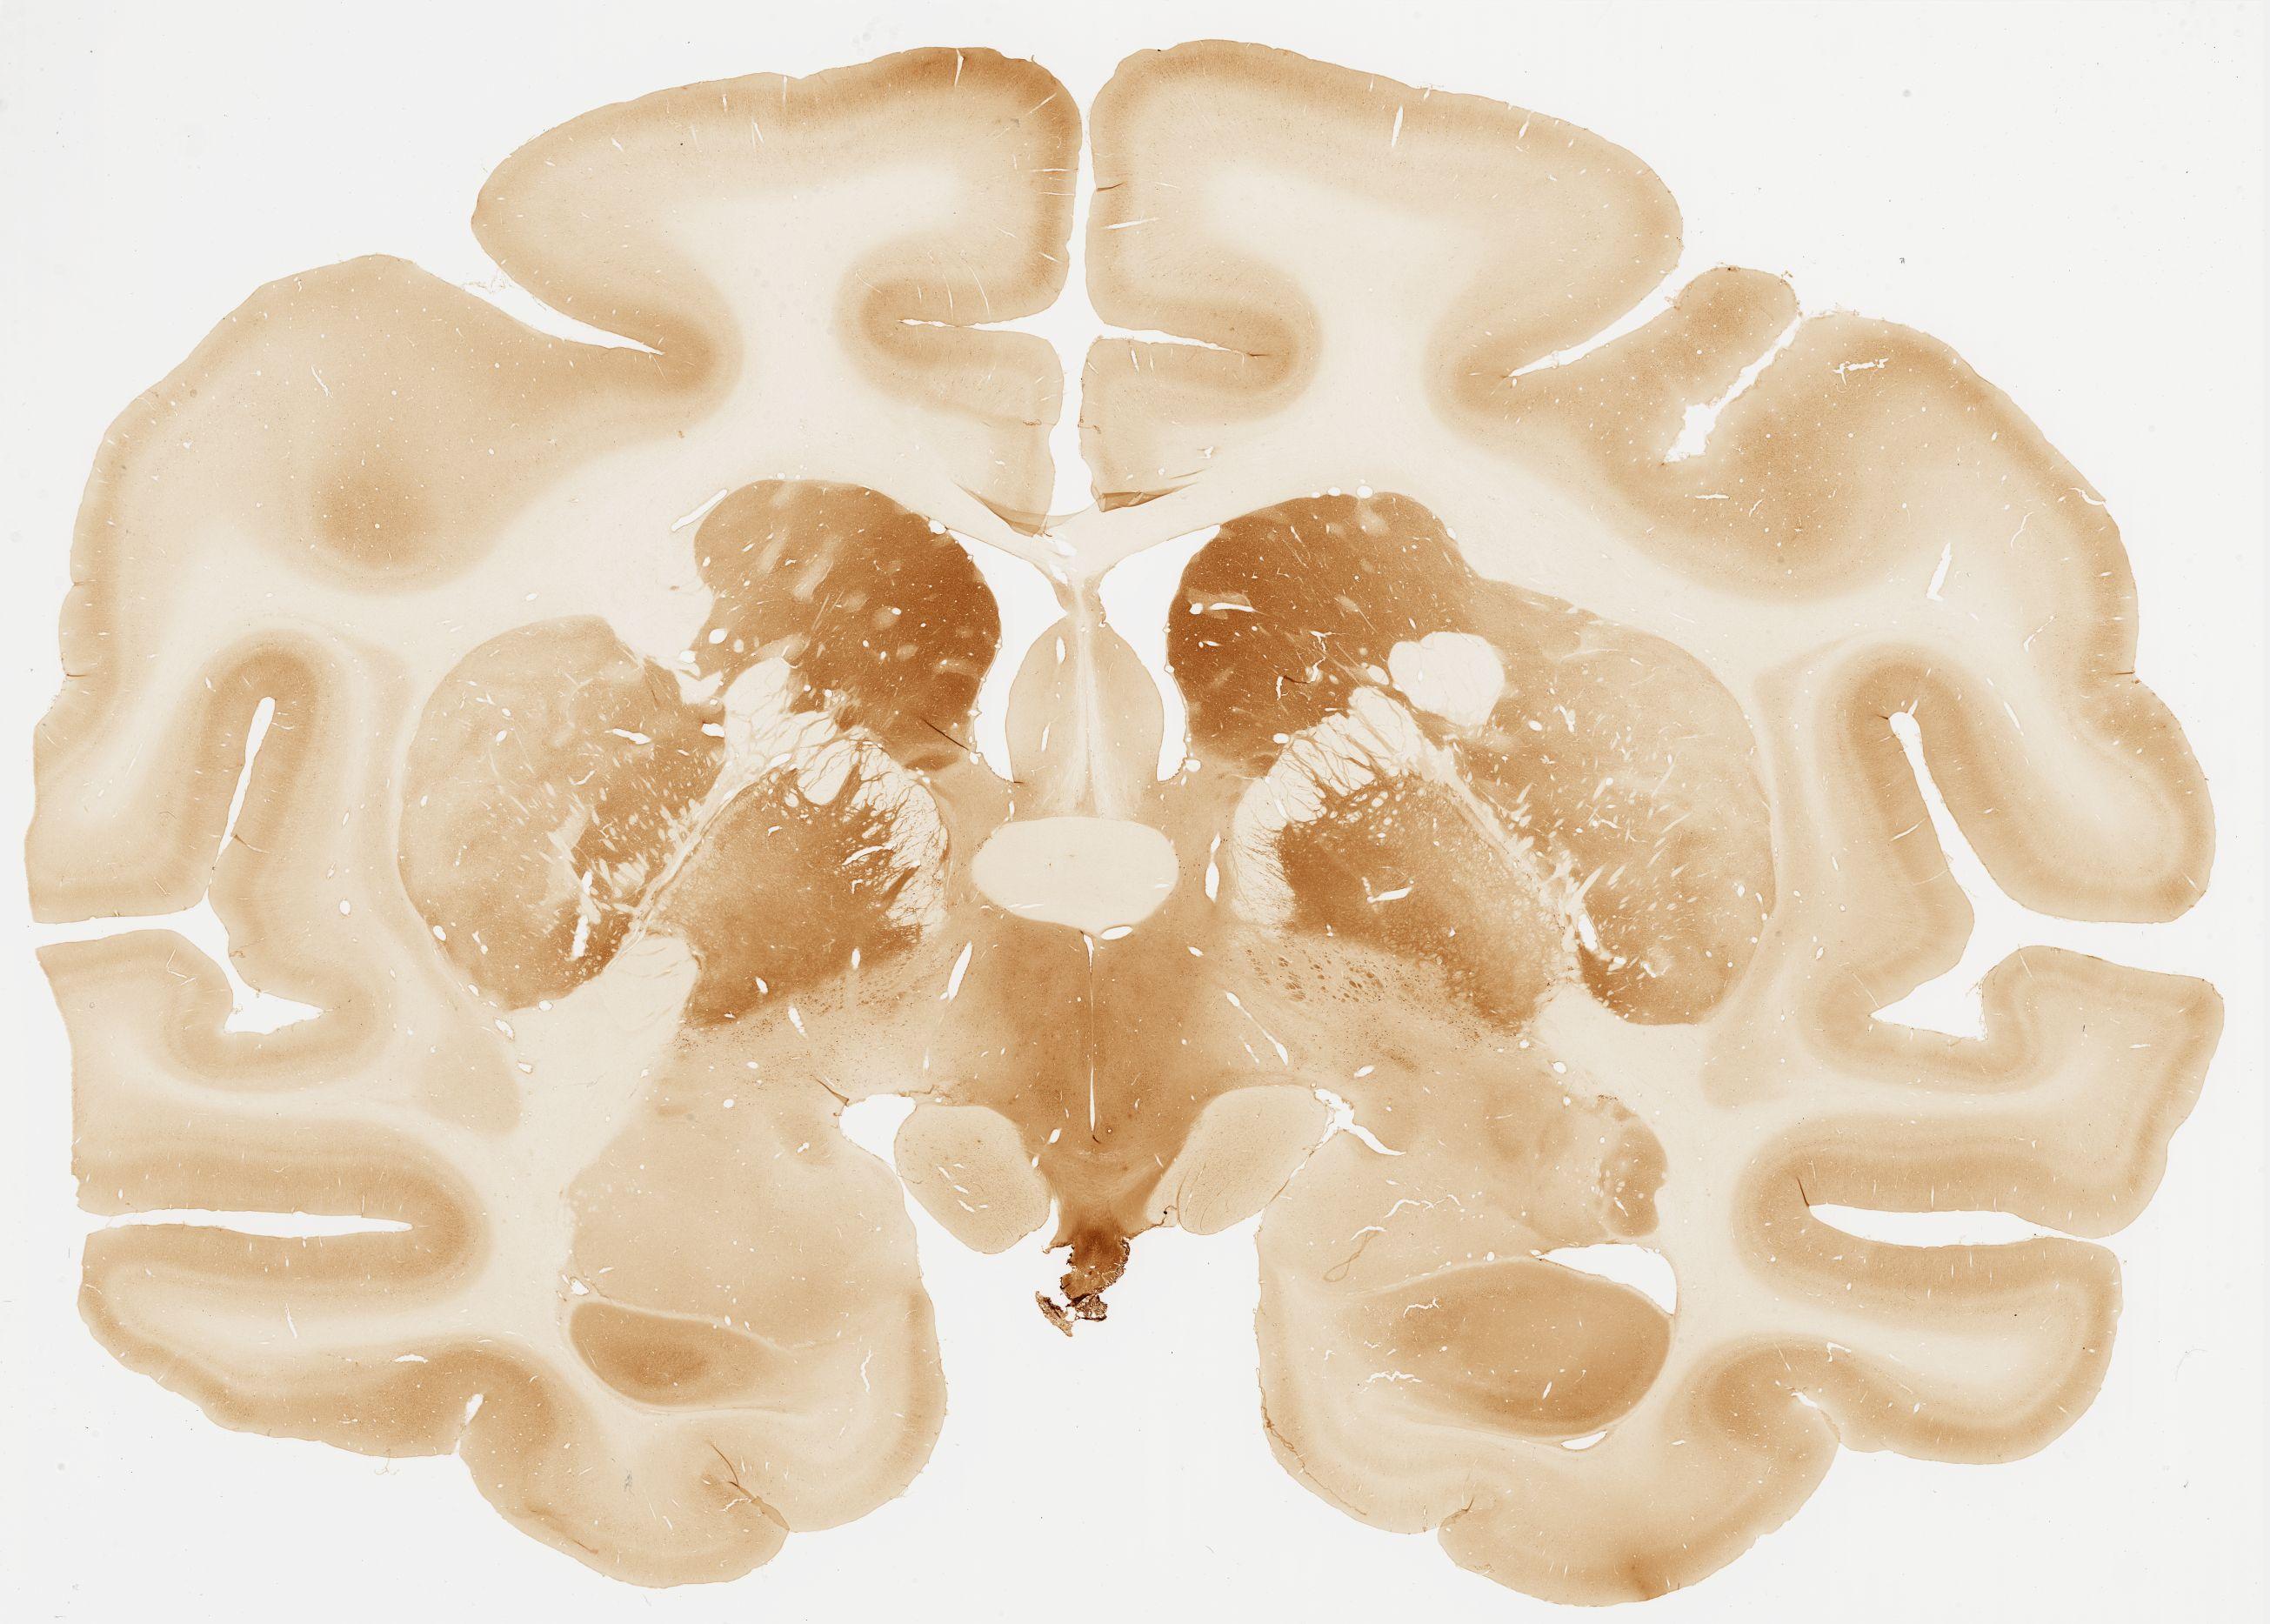

Datasets -> Macaca Fascicularis -> Calb, (Calbindin), coronal, immuno, Whole-Brain, adult

[ Metadata ]   ·   Source: Edward G. Jones

059